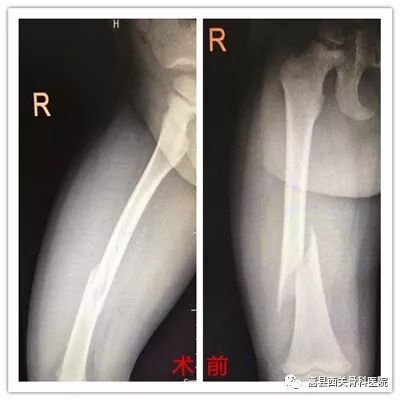

典型病例: